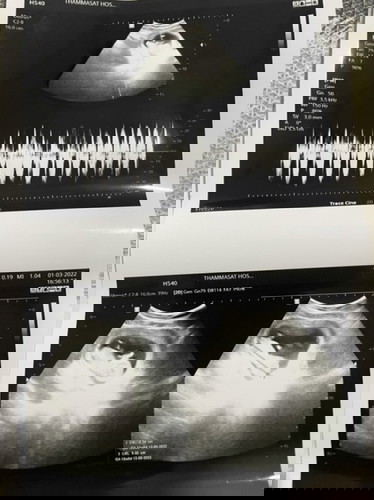

กี่สัปดาห์ถึงจะทราบเพศน้าาา ?

12 w 6d 💛